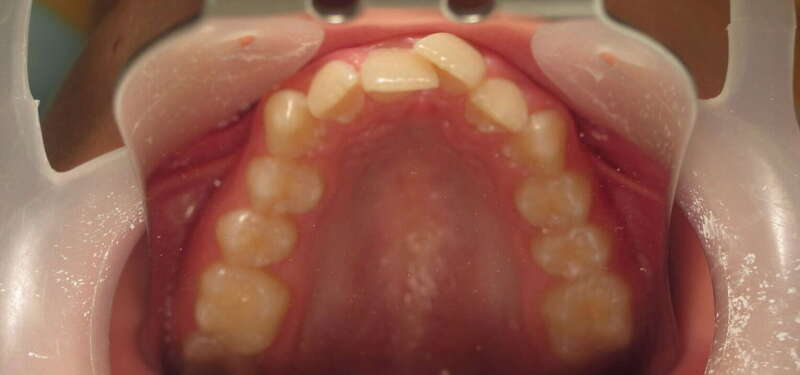

Ce cas d’interception chez un enfant de 8 ans démontre l'efficacité des aligneurs pour corriger des troubles fonctionnels précoces. Le diagnostic présentait des inversions d'articulé provoquant une déviation de la mandibule vers la gauche et un décalage des milieux.

Grâce à une coopération exemplaire et un traitement totalement indolore, l'expansion de l'arcade a permis de recentrer la mâchoire. Cette intervention a littéralement remis la croissance sur les rails, neutralisant le risque d'asymétrie faciale squelettique.

• Correction fonctionnelle : Recentrage immédiat de la mandibule et des milieux inter-incisifs.

• Prévention : Création d'un environnement favorable pour les dents définitives à venir.